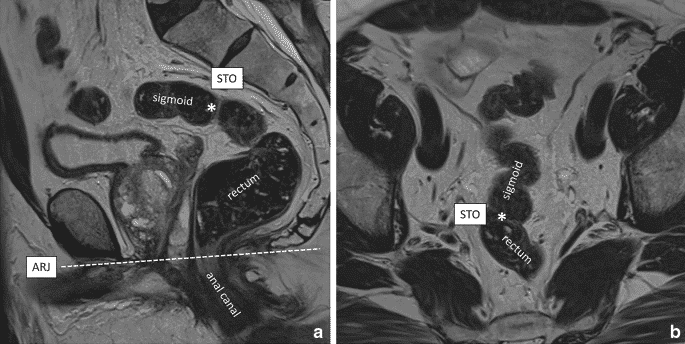

№2. Ректосигмоїдний перехід

- Представляє собою зʼєднання сигмоподібної та прямої кишки.

- Згідно з консенсусом мультидисциплінарної експертної групи, найбільш підходящим анатомічним орієнтиром вважаться sigmoid take-off.

№3. Sigmoid take-off

- Анатомічний орієнтир ректосигмоїдного переходу.

- Виглядає як частина товстої кишки, яка “відходить” від крижової кістки і направляється до переднього частини перехідної складки (як правило, на декілька сантиметрів вище неї).